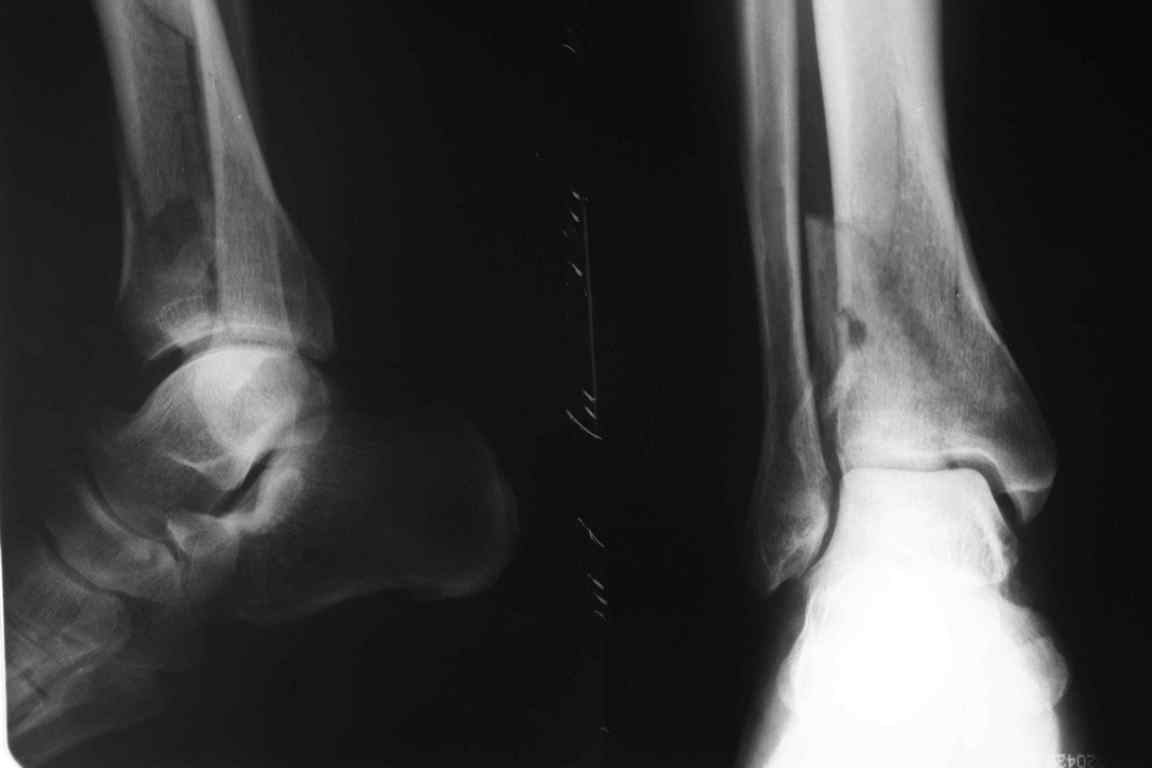

Коллеги, хотелось бы вновь поднять тему переломов пилона.

Прошу помощи в выборе метода оперативного лечения для следующего

больного: мужчина,60 лет, травма от 21.02. Перелом закрытый, из

сопутствующих заболеваний ГБ. Из особенностей - вес пациента 120 кг.

Рентгенограммы в приложении.